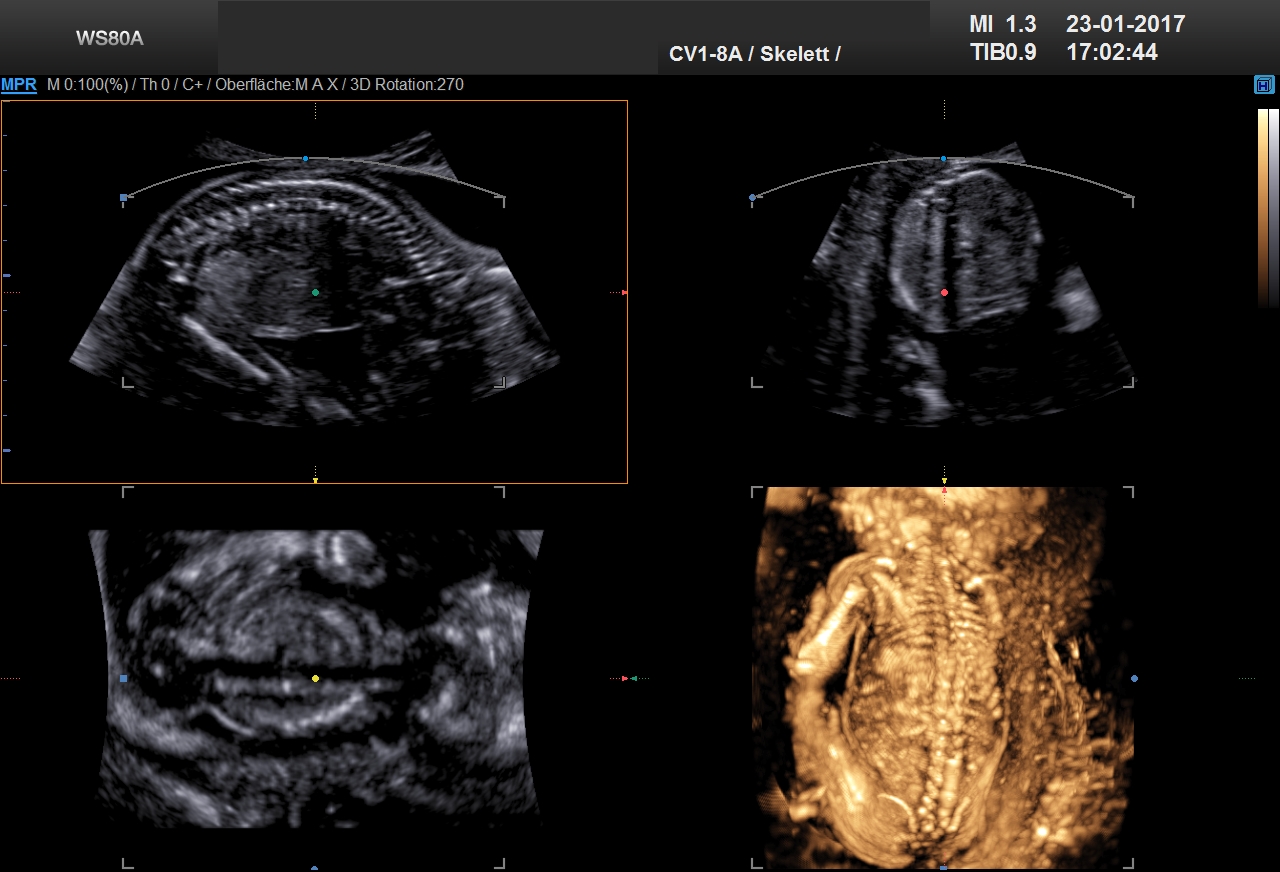

21. Woche